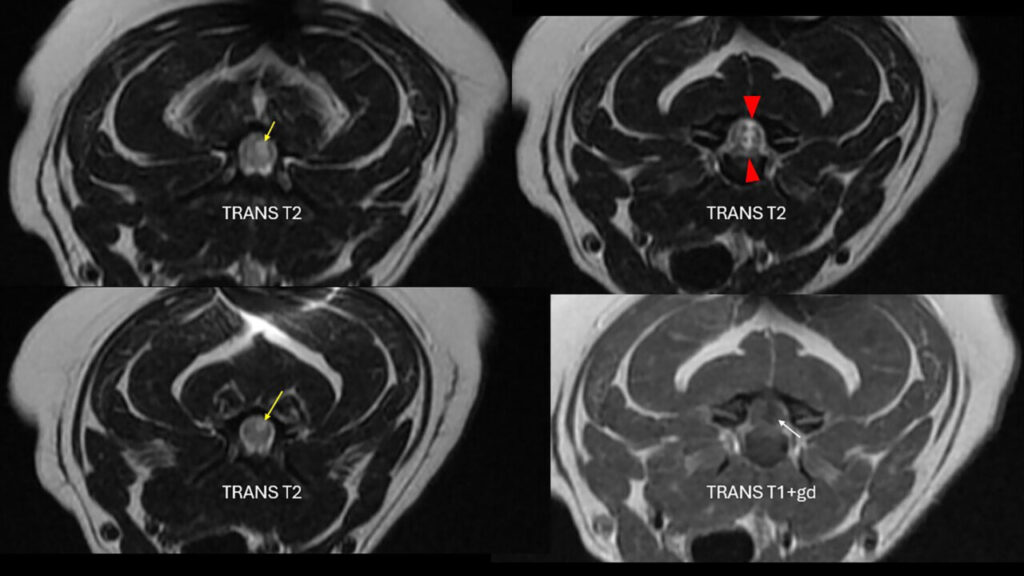

Se hospitalizó para realizar el protocolo diagnóstico con RM de los segmentos medulares comprendidos entre C1-T2. El estudio mediante RM (1,5 T) de la columna cervical se realizó incluyendo las siguientes secuencias: sagitales (T2w, 3D T2, STIR, T1w, T1w+Gd); transversales (T1w, T2w, T1w+Gd); dorsales (FIESTA, 3D). Se observó una pérdida de volumen del disco C3-C4 que mantenía una señal correcta en T2w. Justo dorsal al disco y, a nivel intramedular, se apreció una marcada lesión lineal hiperintensa en T2w y STIR e hipointensa en T1w que atravesaba la médula espinal en sentido dorsoventral, ligeramente lateralizada a la derecha. Tanto craneal como caudal a dicha lesión, hasta la mitad caudal de C3 y a la mitad craneal de C4, se vio una señal intramedular, hiperintensa en T2w y STIR, pero más difusa, también lateralizada a la derecha y dorsal. Este estudio no mostró evidencia de material extradural que causara compresión medular (imágenes 3A y 3B).

Imagen 3. Caso 2. A) RM, cortes sagitales utilizando distintos tipos de secuencias. Se aprecia un trayecto en dirección dorsal desde el espacio IV C3-C4 hasta el parénquima medular (flechas amarillas; sag 3D T2 cube) que muestra señal hiperintensa craneal y caudalmente a dicho espacio (flecha roja; sag T2). El disco C3-C4 muestra un menor volumen (puntas de flecha azules; sag STIR) y no se evidencia la presencia de material degenerado compresivo en el canal vertebral (sag T1+gd). Resonancia magnética informada por ProtonVet. B) RM, cortes transversales en T2 y T1 poscontraste. Se observan las zonas de hiperintensidad en T2 craneal y caudalmente (flechas amarillas) al trayecto que va en dirección ventro-dorsal (puntas de flecha rojas) que podrían ser compatibles con zonas de gliosis, edema o malacia. En T1, la zona justo dorsal al disco, se aprecia hipointensa (flecha blanca). Resonancia magnética informada por ProtonVet.